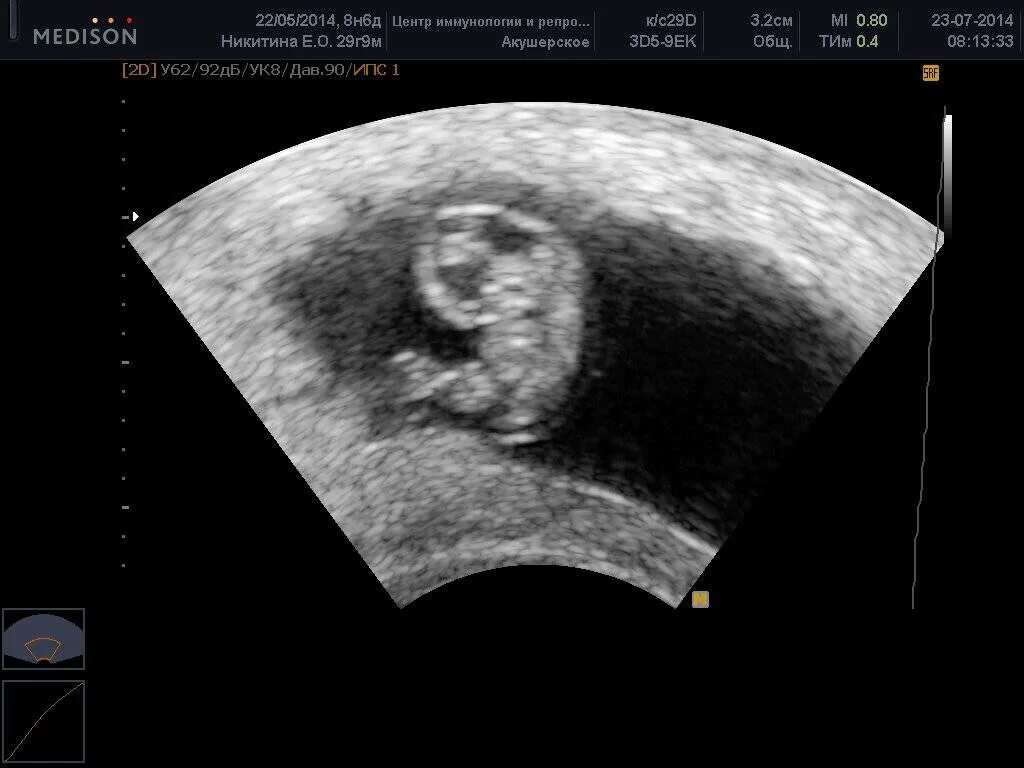

8 недель беременности вторая беременность